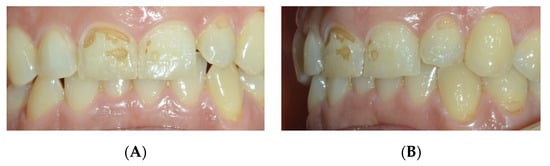

| Gotouda et al. (2017) [61] | Study in vitro | Reaction of different types of dentin and enamel to carbonated beverages. | X-ray microdiffraction analysis showed a wide range of white stain areas in the enamel, ranging from barely perceptible to nearly complete decay. | This research provides fundamental crystallographic information that will soon be used in preventive dentistry. |

| Kono et al. (2019) [71] | Study in vitro | Micro-FTIR spectroscopic analysis of teeth sections to clarify chemical processes of dental caries. | X-ray microdiffraction analysis showed a wide range of white stain areas in the enamel, ranging from barely perceptible to nearly complete decay. | This study demonstrated the range and normalcy of dental enamel features. |